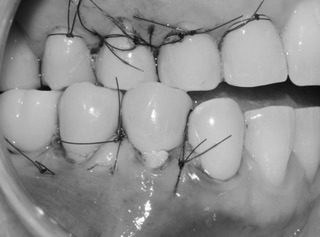

Proceso del tratamiento: